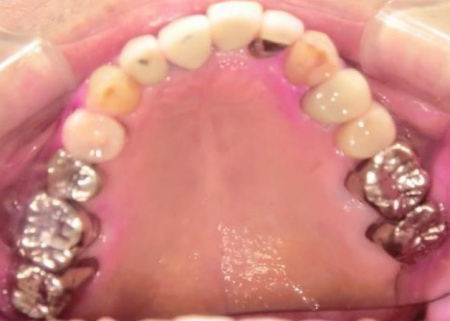

70代男性 右下奥歯を抜いてインプラント治療で噛み合わせを回復した症例

拝見したところ、右下奥歯(第2小臼歯)の周辺組織に炎症が広がり、歯茎が赤く腫れていました。

まず、右下奥歯(第2小臼歯)を抜き、骨が治癒するのを待ってから、インプラントを埋入します。

インプラントと顎の骨がしっかりと結合したら、精密な型取りを行い、インプラント上部に装着する最終的な被せ物を作製しました。

最後に完成した被せ物を装着し、見た目や噛み合わせに問題がないことを確認して、治療を終了しています。